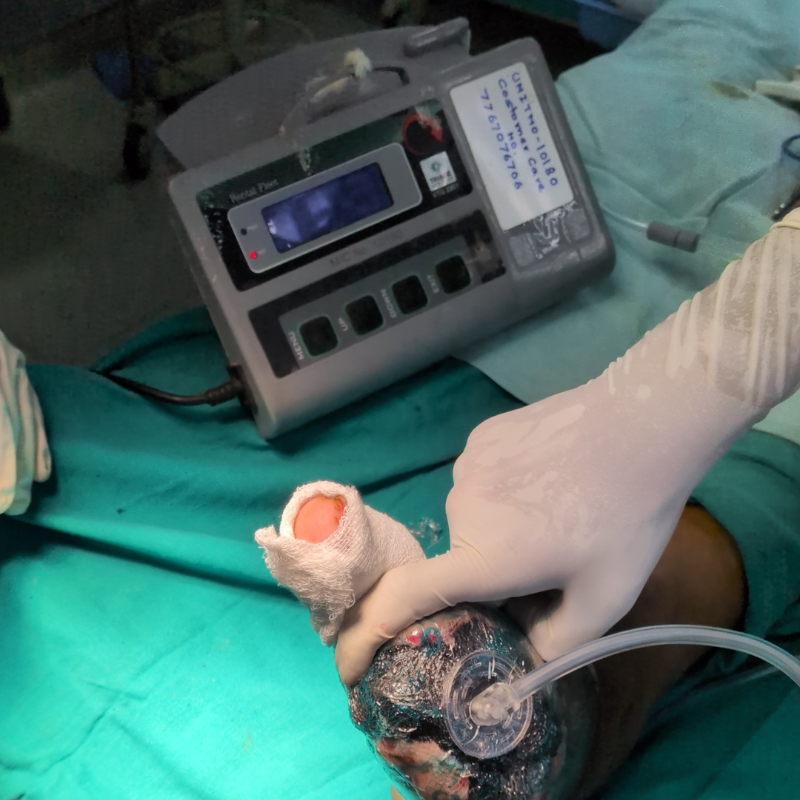

Poor circulation and high blood sugar create an environment prone to infections and impaired healing. If left untreated, these injuries can turn into non-healing ulcers and, in severe cases, lead to gangrene (black foot), where tissue dies and amputation may be necessary.

If you’re a diabetic, schedule a consultation with our team for a detailed diabetic foot assessment.